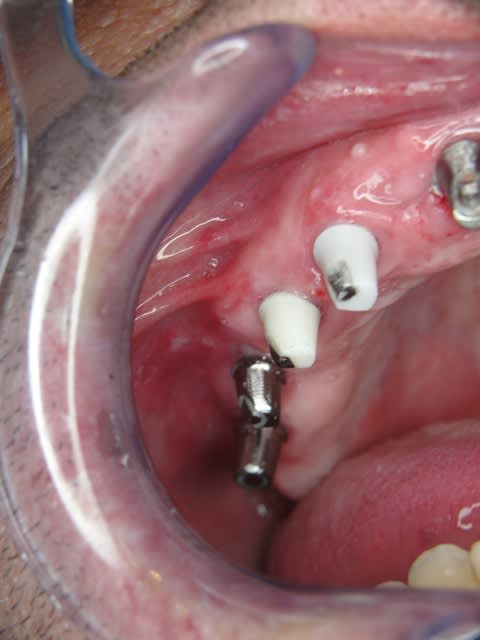

3ème photo: radio d´un patient âgé de 73 ans qui souhaitait avoir des dents fixées.Comme on l´observe il n a plus de place après les foramines mentales.Nous avons donc utilisé juste l´os interforaminal. Nous avons suivi le concept du prof. Nentwig qui consiste à pouvoir ajouter 2 dents dans chaque quadrant dans la mandibule.

Je sais bien que 8 implants auraient suffit cependant 10 ont été posés.Nous voulions remplacer chaque racine avec un implant.

Le patient n a jamais eu de problèmes ( juste avec une hygiène buccale normale, brosse à dents).